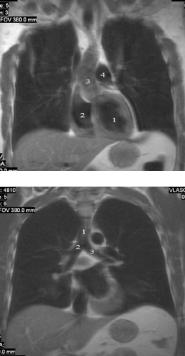

Рис. 14. Т1-ВИ органов средостения

в аксиальной проекции на уровне восходящей аорты: 1 – восходящая аорта,

2 – ствол легочной артерии,

3 – правая легочная артерия,

4 – нисходящая часть аорты

5 – верхняя полая вена,

6 – ветвь левой легочной артерии, 7 – просвет правого

промежуточного бронха, 8 – просвет левого верхнедолевого бронха, 9 – непарная вена

Рис. 15. Т1-ВИ органов средостения

в аксиальной проекции на уровне корня аорты:

1 – корень аорты,

2 – выходной отдел правого желудочка, 3 – левое предсердие с

впадающими в него верхними легочными венами

Рис. 16. Т1-ВИ органов средостения в

коронарной проекции на уровне корня аорты:

1 – полость левого желудочка,

2 – полость правого желудочка, 3 – восходящая аорта с

отходящими от нее правым плечеголовным стволом и левой общей сонной артерией, 4 – ствол легочной артерии

Рис. 17. Т1-ВИ органов средостения

в коронарной проекции на уровне бифуркации трахеи:

1 – просвет трахеи,

2 – правый главный бронх,

3 – левый главный бронх